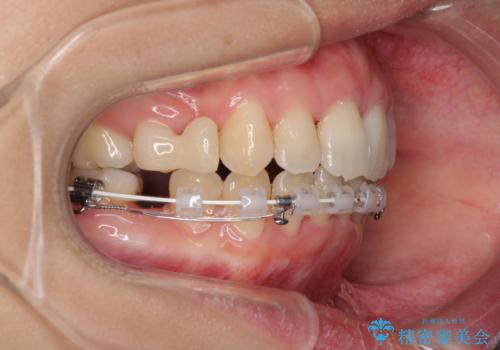

- 矯正装置

- ハーフリンガル

舌の突出癖が強く、口元を引っ込める力に拮抗してしまい、抜歯スペースを閉じるまでに時間がかかりました。

また途中出産もありましたが、無事に治療を終えることができました。